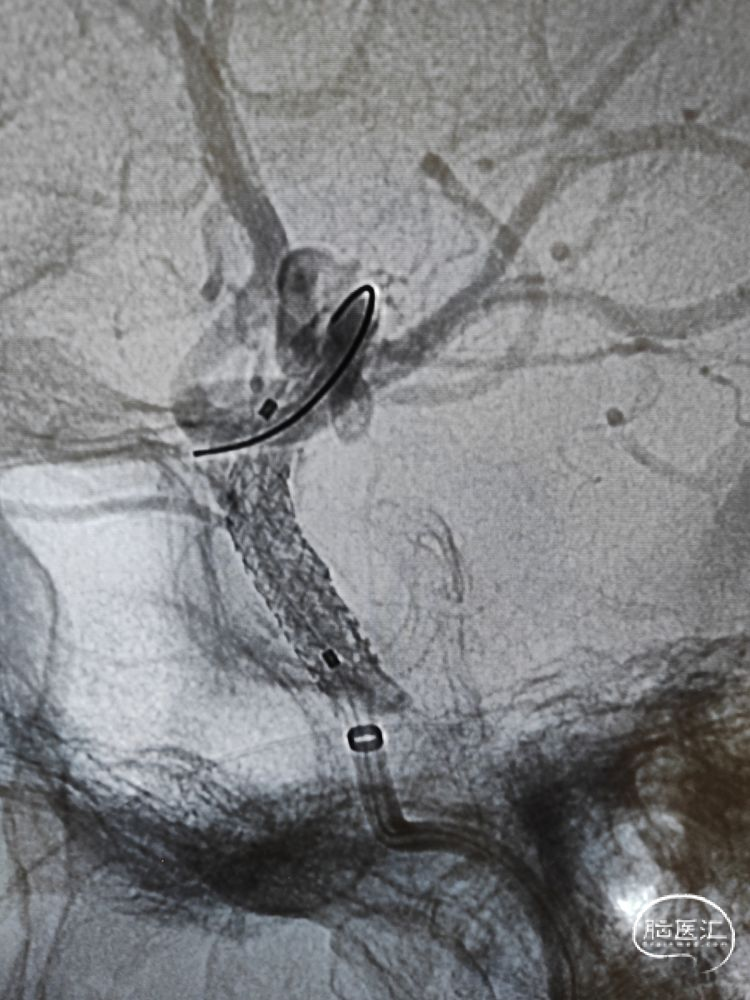

支架到位及释放:

在颅内支撑导管的支持下,沿微导丝将4.0mm*13mm Bridge椎动脉雷帕霉素靶向洗脱支架送至狭窄部位,支架到位比较顺利,通过狭窄处支架略有卡顿、微导丝有些回退,支架近端定位在接近正常段管径4mm处,略高于额定压扩张球囊释放支架,球囊缓慢泄张后造影提示支架内血流通畅,支架完全张开贴壁,局部无残留狭窄。